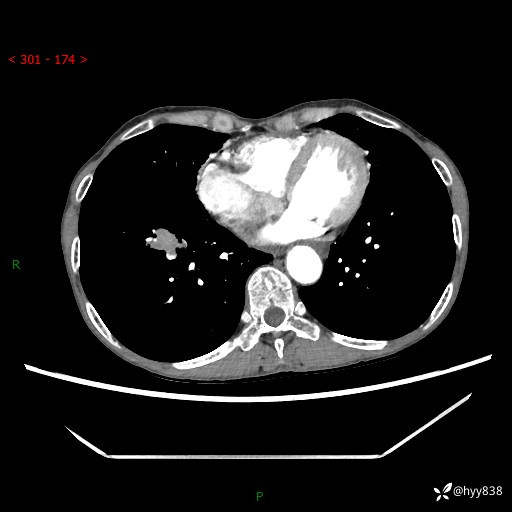

【患者信息】:69岁/女

【主诉】:发现肺占位3天余

【现病史及既往史】:患者3天余前因既往肺气肿复查胸部CT发现“右肺下叶结节、双肺多发结节、双肺门及纵膈淋巴结增大”,平素偶有咳白色粘液痰,下肢乏力,无明显低热、盗汗、咯血、胸痛、喘气等不适,今为求明显结节性质遂来我院门诊就诊,门诊以“孤立性肺结节”收治入院。 起病以来,患者精神饮食睡眠一般,大小便正常,体力无明细变化,体重近年来较前下降。

【检查】:胸部CT增强